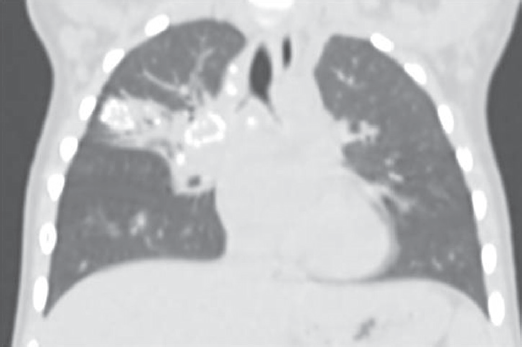

The problem of young children tuberculosis in Russian Federation (RF) still remains actual because of high-level spread of disease between adults and anatomical and physiological features of this period of childhood. The young children morbidity in Saint Petersburg, 2015-2017 became 7.1-5.3 of 100,000 population. It is typical for the age group from 0 to 3 years that tuberculosis development often becomes into the state of active disease and does not stop as latent infection. Our research includes children of early age whose tuberculosis has been diagnosed in 2012-2017 – totally 101 children. One third of the patients were not vaccinated with the BCG vaccine, moreover 41.9% were not vaccinated because of perinatal contact with HIV and 22.5% because of perinatal contact with HIV + hepatitis C. Each second child related to social risk group. Contact with MBT expectorator has been found for 64% of children: drug resistance for at least one drug has been met in 70% cases, including 19% MDR-TB and 11% XDR-TB. Immunology diagnosis analysis showed up that at the moment of the disease detection the tuberculin skin test in 93% cases was positive, but often moderately expressed, meanwhile the Diaskintest was positive in 92% cases, mainly hyperergic or expressed. Objective diagnosis for 79% patients showed symptoms of intoxication of different degrees, for 50% – micropolyadenia, local symptoms – only for 13%. Structure of diagnosis contained mainly intrathoracic lymph nodes tuberculosis (67%), gene ralized forms – 9%, extrapulmonary – 1%. Complicated tuberculosis has been observed in 38% cases. After treatment recovery has been achieved for 98 children, but also 3 lethal cases occurred – all for non-vaccinated infants in case of severe concomitant disease. Conclusion: nowadays development of active tuberculosis in young children is caused by increasing quantity of BCG-unvaccinated newborns – mostly because of perinatal HIV-contact, and poor social conditions.